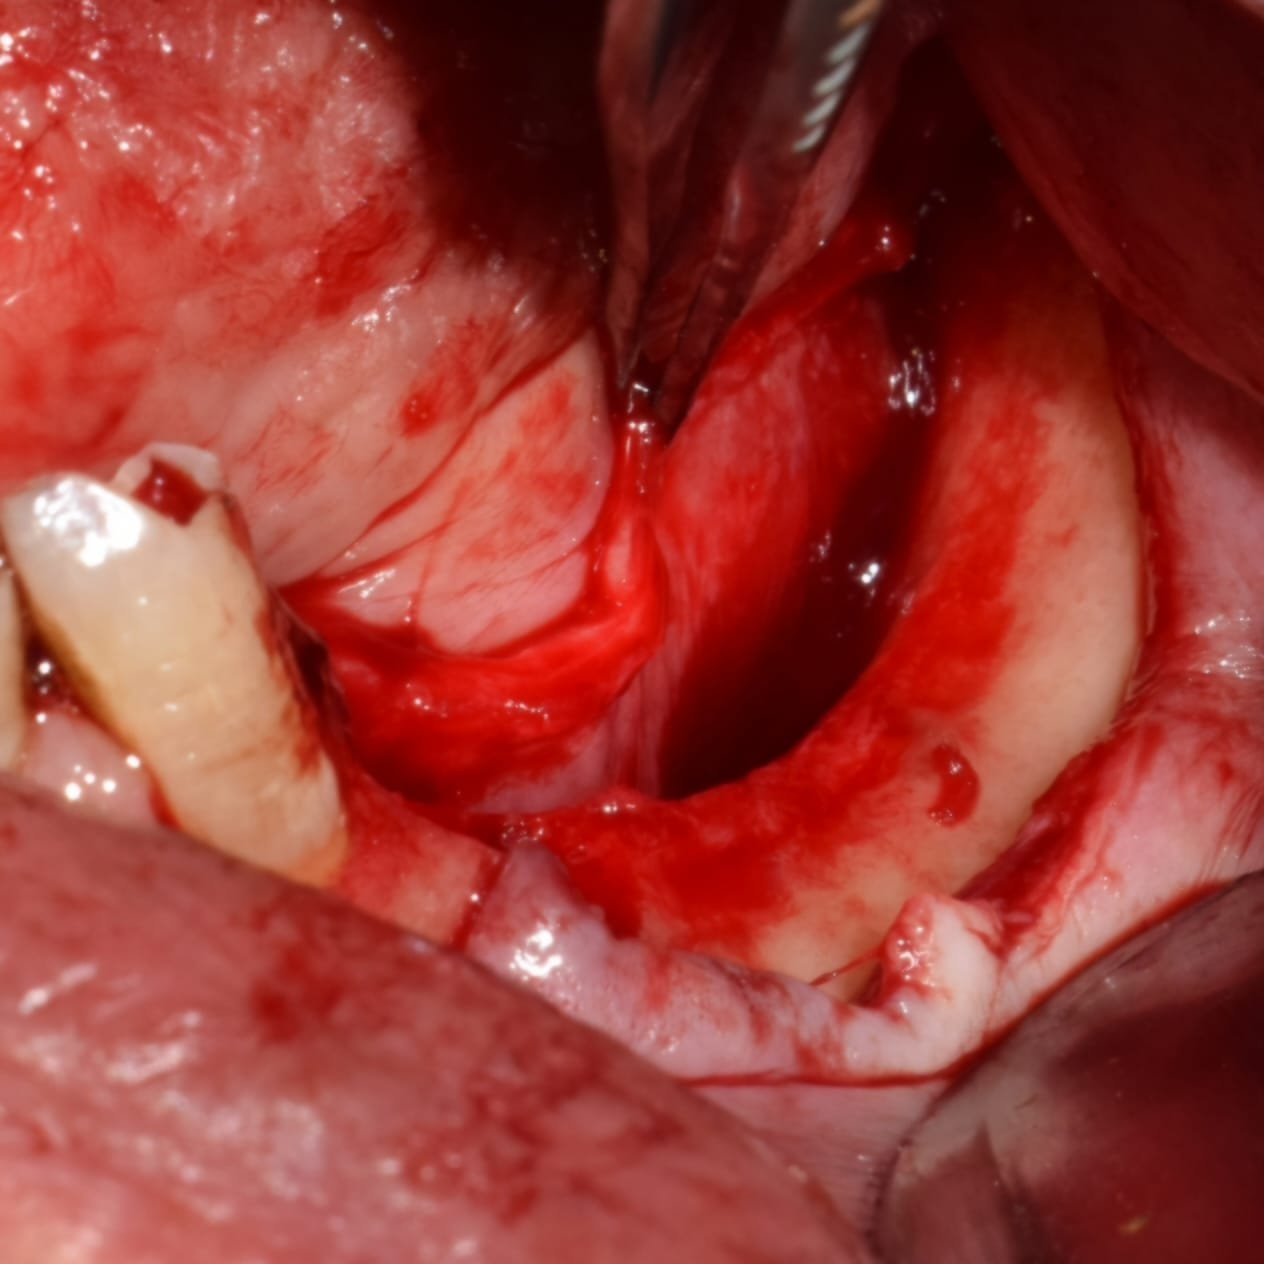

• Diseño de colgajos para ROG vertical.

• Manejo de tejidos blandos.

• Decorticalización y preparación del lecho receptor.

• Obtención de hueso autólogo

• Manejo de biomateriales.

• Colocación de la barrera de zirconio.

• Fijación: secuencia correcta de atornillado.

• Control de estabilidad primaria.

• Cierre por planos y manejo de la tensión.

• Claves quirúrgicas para minimizar complicaciones.

• Suturas.